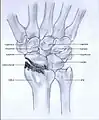

Post-traumatic osteoarthritis can be classified into four stages.[1][6] These stages are similar between SLAC and SNAC wrists. Each stage has a different treatment.

- Stage I: the osteoarthritis is only localized in the distal scaphoid and radial styloid.

Stage I